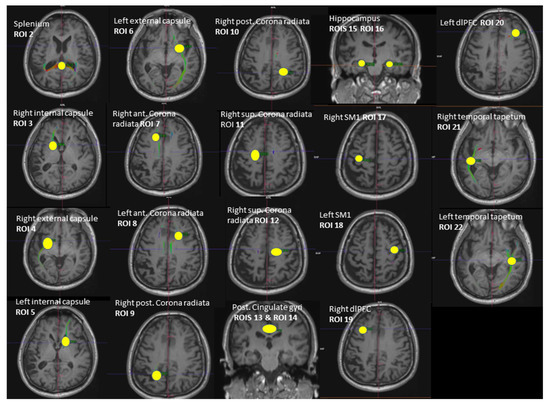

2.2. Brain Imaging and 1H-MRS

| ROI | Anatomical Region | FA in ROI | Mean HC | Mean MCI | Test | Test Statistic Value | p-Value |

|---|---|---|---|---|---|---|---|

| ROI 1 | All diffusion tracts | FA 1 | 0.476 | 0.467 | t-test | 2.789 | 0.007 * |

| ROI 2 | Splenium of corpus callosum | FA 2 | 0.554 | 0.549 | M-W | 356.0 | 0.846 |

| ROI 3 | Right internal capsule | FA 3 | 0.438 | 0.432 | M-W | 302.5 | 0.271 |

| ROI 4 | Right external capsule | FA 4 | 0.414 | 0.408 | t-test | 0.834 | 0.408 |

| ROI 5 | Left internal capsule | FA 5 | 0.433 | 0.438 | M-W | 304.5 | 0.286 |

| ROI 6 | Left external capsule | FA 6 | 0.436 | 0.414 | t-test | 3.058 | 0.003 * |

| ROI 7 | Right corona radiata anterior | FA 7 | 0.474 | 0.461 | t-test | 1.542 | 0.129 |

| ROI 8 | Left corona radiata anterior | FA 8 | 0.471 | 0.456 | t-test | 2.024 | 0.048 * |

| ROI 9 | Right corona radiata posterior | FA 9 | 0.480 | 0.469 | t-test | 1.229 | 0.224 |

| ROI 10 | Left corona radiata posterior | FA 10 | 0.479 | 0.468 | t-test | 0.983 | 0.330 |

| ROI 11 | Right corona radiata superior | FA 11 | 0.477 | 0.466 | M-W | 273.000 | 0.110 |

| ROI 12 | Left corona radiata superior | FA 12 | 0.487 | 0.461 | t-test | 2.207 | 0.032 * |

| ROI 13 | Right cingulate gyri post | FA 13 | 0.446 | 0.432 | t-test | 1.55 | 0.131 |

| ROI 14 | Left cingulate gyri post | FA 14 | 0.454 | 0.441 | t-test | 1.393 | 0.169 |

| ROI 15 | Right hippocampal cingulate | FA 15 | 0.428 | 0.417 | t-test | 1.321 | 0.192 |

| ROI 16 | Left hippocampal cingulate | FA 16 | 0.425 | 0.419 | t-test | 0.637 | 0.527 |

| ROI 17 | Right sensorimotor cortex | FA 17 | 0.448 | 0.440 | t-test | 0.925 | 0.359 |

| ROI 18 | Left sensorimotor cortex | FA 18 | 0.430 | 0.429 | t-test | 0.086 | 0.931 |

| ROI 19 | Right dorsolateral prefrontal cortex | FA 19 | 0.408 | 0.367 | t-test | 2.455 | 0.017 * |

| ROI 20 | Left dorsolateral prefrontal cortex | FA 20 | 0.398 | 0.377 | t-test | 2.103 | 0.040 * |

| ROI 21 | Right temporal tapetum | FA 21 | 0.442 | 0.429 | t-test | 1.644 | 0.106 |

| ROI 22 | Right temporal tapetum | FA 22 | 0.450 | 0.433 | t-test | 2.151 | 0.036 * |